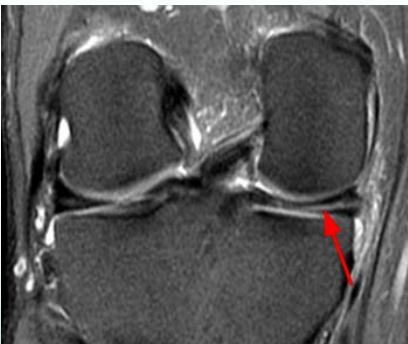

Diagnostic Studies

MRI